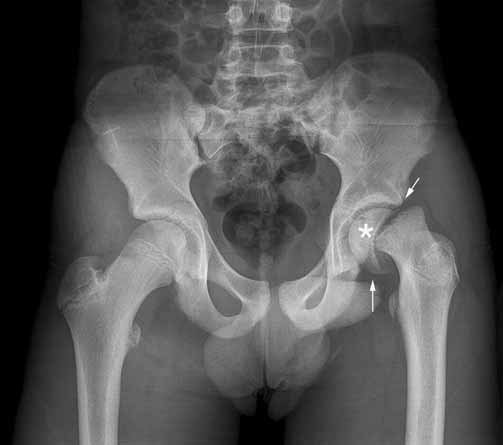

انزلاقُ مشاش رأس الفخذ Slipped Capital Femoral Epiphysis هو انزلاق أو انفصال في نهاية عظم الفخذ عند صفيحة النمو في مفصل الورك. قد يكون سببُ هذا الاضطراب ضعف نمو مفصل الورك. وقد يكون العرض الأول هو التيبس أو الألم الخفيف في الورك، يستند التشخيصُ إلى الصور الشعاعية للصدر، وبعض الاختبارات التصويرية الأخرى في بعض […]

داء ليغ كالفيه بيرثيز هو مرض يصيب الأطفال يحدث عند إعاقة وصول إمداد الدم مؤقتًا إلى الجزء الكروي (رأس الفخذ) من مفصل الورك وتبدأ العظمة في الاضمحلال. تتفكك هذه العظمة المصابة بالضعف تدريجيًّا وقد تفقد شكلها المستدير. ويعيد الجسم إمداد الدم إلى الكرة في آخر الأمر إلى أن تُشفى. لكن إذا لم تسترجع الكرة […]